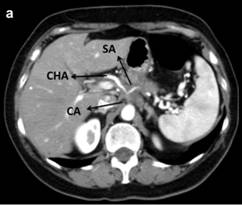

Ultrasonography of the abdomen revealed a hypoechoic 30x40 mm mass in the pancreatic body. Abdominal CT scan confirmed a solid heterogeneous mass of the pancreatic body, without cystic component. No radiologic signs of metastasis were found (Figure 1). Vascular reconstruction of CT scan showed a suspicious infiltration of the common hepatic and the splenic arteries with a total occlusion of the celiac trunk with a normal flow thought the gastro-duodenal artery. Furthermore, multiples atheromatous plaques with calcification were seen in the aorta. Similar findings were found in the pancreatic magnetic resonance. In the endosonographic study, the mass presents a high vascularization, confirming the infiltration of the major arteries at the origin of the celiac trunk. In the same study a biopsy was performed, compatible with adenocarcinoma.

Figure 1. Preoperative CT scan. a. A 4 cm tumor in the body of the pancreas narrowing of the vessels at the origin of the celiac axis due to tumor encasement. b. Superior mesenteric artery is not involved. CA: celiac axis; CHA: common hepatic artery; SA: splenic artery; SMA: superior mesenteric artery |